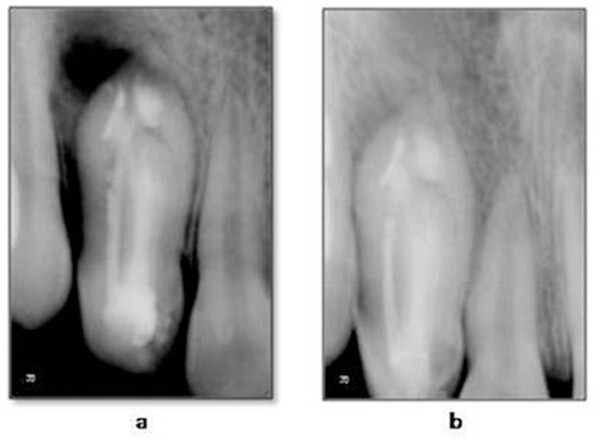

Для облегчения поиска каналов использовалось увеличение. Получен доступ к пульповой камере, проведена рентгенограмма с файлом K-flex № 10 в канале. Рабочую длину определяли с помощью K-file № 10 (рисунок 1D), механическая обработка каналов проводилась K-file № 35. Поскольку консервативное лечение апикальной области одного из каналов было затруднено, мы запланировали проведение апикальной хирургии и ретроградного пломбирования МТА (минерал триоксид агрегат) с обтурацией термопластифицированной гуттаперчией. Результаты регулярных анализов крови находились в пределах нормы. При последующем назначении зуб был подготовлен для хирургического вмешательства. В ходе операции был отслоен слизисто-надкостничный лоскут и сделано отверстие в проекции апекса (рисунок 1Е). После полного кюретажа мягких тканей и последующего удаления грануляционной ткани проведена коррекция(сошлифовывавание) твердых тканей апекса. После тщательной очистки было проведено ретроградное пломбирование МТА (ProRoot®, DENTSPLY, www.denstply.com) (рисунок 1F), за которым последовала обтурация термопластифицированной гуттаперчей (Endo@pex, Cordless Obturation System, DXM, Korea, www.dxm.co.kr) (рисунок 2A). Лоскут уложен на место, рана ушита шелковой нитью 5-0.

При последующем визите через неделю после операции был снят шов, заживление проходило без осложнений. Через 1,5 месяца после лечения пациентка не предъявляла жалоб. На контрольной рентгенограмме можно оценить признаки регенерации твердых тканей в перирадикулярной области (рис. 2b). Последующее рентгенографическое исследование, проведенное через 6 месяцев, показало полное восстановление.